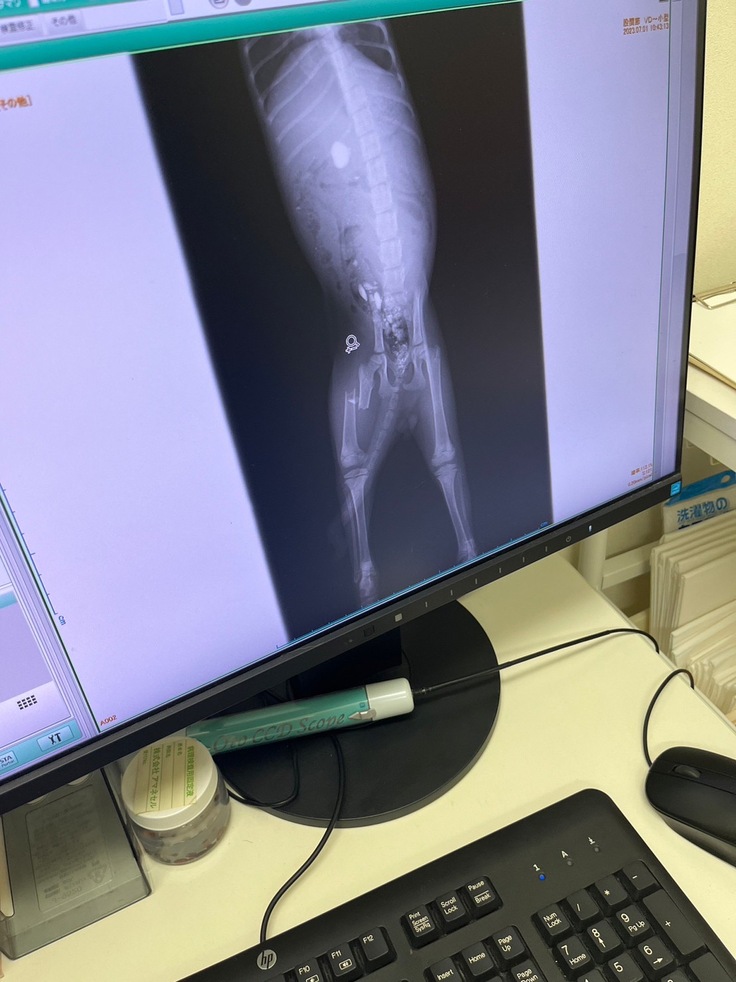

●2023/7/1

近くの動物病院受診。

大腿骨の骨折、胃に砂利や石がある事がわかりました。

手術が必要で札幌の動物病院を紹介して頂きました。

その日の夕方頃札幌の動物病院受診。

獣医師の説明によれば、

「肋骨にも骨折がある事がわかりましたが、既に治りつつあるので問題ない。」

「細かい砂利は自然に便と一緒に排出されると思うが、胃にある1センチ程の小石は放置すると腸閉塞の危険性がる。」

「一旦骨折は保留、1週間様子を見てほしい」

という事でした。

右は1週間前のレントゲンで、左が1週間後のレントゲン画像です。

砂利も小石もきれいに便と一緒に出たようで、お腹を切る必要はなくなりました!

あとは骨折の整復手術のみ...